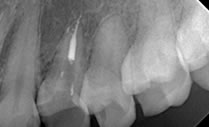

2008年4月

来院時:側方加圧根菅充填(ポイント根充)によるper咬合痛あり。根菅治療スタート。

2008年6月

オブチュレーションシステムを用いて根菅充填:根尖までオブチュレーションガッタが充填されているのがわかります。根尖孔から少しオーバーしているのがポイントです。